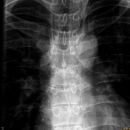

Densfraktur